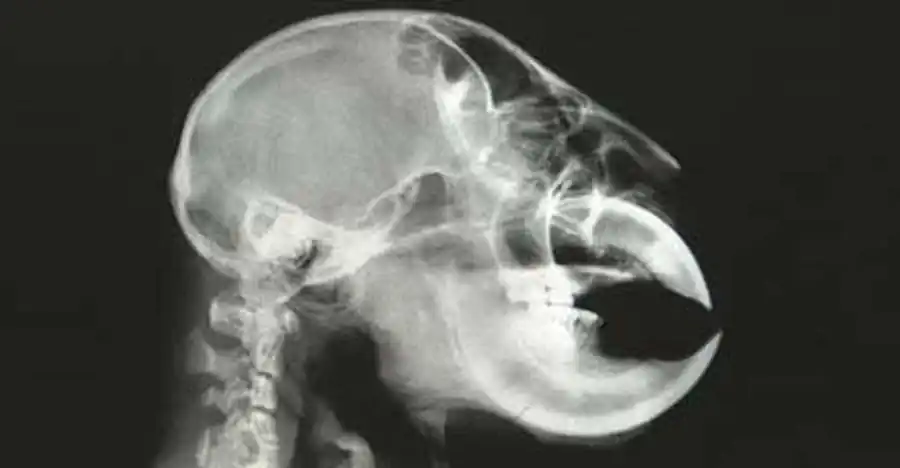

Голова у лемура-руконожки довольно крупная, округлая, лицевой отдел укорочен. Голову украшают два огромных глаза и большущие ложковидные уши, не покрытые шерстью.

Зубки-резцы также довольно крупные, изогнуты и отделены большим промежутком от коренных зубов. Смена молочных зубов уносит клыки с собой, но резцы растут в течение всей жизни этого маленького юркого зверька.

У руконожек задние ноги намного длиннее передних. Как у большинства приматов, на ступнях большой палец противопоставлен всем остальным, а на кистях это противопоставление практически отсутствует. Ногти на всех пальцах когтеобразные, кроме больших пальцев задних конечностей - там они плоские.

Но самой удивительной особенностью руконожек ай-ай является третий палец на его передних конечностях. С помощью этого пальца маленький зверек может делать множество различных операций.